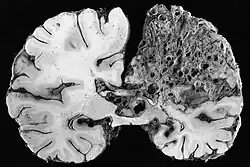

- Kavernom (Cavernöses Hämangiom)

- arteriovenöse Malformation (AVM)

Sie stellen insbesondere im Gehirn ein Blutungsrisiko dar.